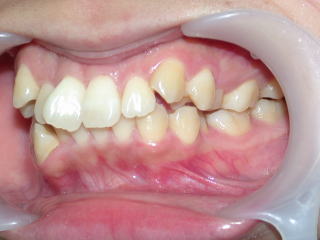

2022年7月25日初診、20代女性の叢生症例 (新潟県長岡市要町 要町歯科 歯科矯正 歯列矯正)

前歯のデコボコが気になる、とのことです。

2023年9月11日